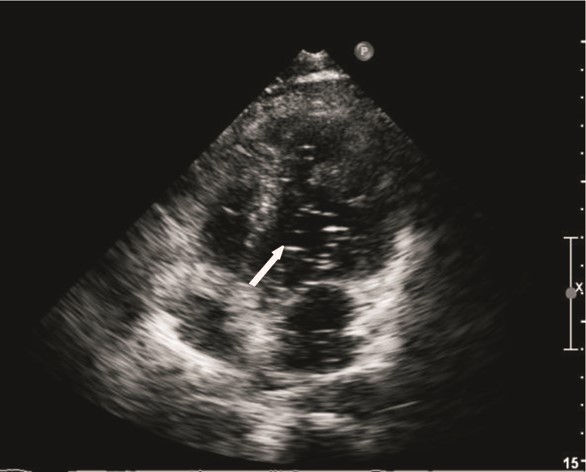

患者男性,25岁,因“突发抽搐后摔倒3 h余”于2014年2月23日诊断“外伤性硬膜下血肿”入我院神经外科,否认既往重大疾病史。急诊头颅计算机断层扫描(computed tomography,CT)及核磁共振成像(magnetic resonance imaging,MRI)均提示“左侧额颞部少量硬膜下血肿”。入院时患者浅昏迷,躁动不安,格拉斯哥昏迷评分(glasgow coma scale,GCS)11分,双侧瞳孔等大,光反射灵敏,两肺听诊未闻及明显干湿啰音,心律齐,无明显杂音,四肢均有活动,杵状指。入院后患者氧饱和度偏低,不吸氧时指脉氧饱和度波动在85%~90%之间,血常规:白细胞计数 10.4×109 L-1、中性粒比例 76.4%、血红蛋白 153 g/L,肝肾功能均正常范围,考虑患者有杵状指,予预约心脏彩超。入院第二日(2月24日),患者神志转清,有指令动作,对答切题,已可下床活动。2月27日患者在家属搀扶下上厕所时,突发心搏骤停,当时立即予以气管插管以及持续胸外心脏按压等心肺复苏抢救,约110 min左右,患者恢复自主心律并转入ICU进一步抢救及治疗。入ICU时患者双侧瞳孔等大,光反射存在,并随即出现四肢躁动,遂予持续镇痛镇静治疗,并予亚低温脑保护(头部冰帽及盐酸氯丙嗪+异丙嗪静脉维持,维持体温在34 ℃左右),小剂量去甲肾上腺素 维持MAP在90 mmHg(1 mmHg=0.133 kPa)左右,机械通气支持等治疗,患者氧合、循环基本稳定,亚低温治疗48 h左右(3月1日)予复温,患者有自主睁眼,四肢均有活动,期间予床边心脏超声检查(采用右侧锁骨下静脉注射5%碳酸氢钠溶液+维生素C微泡造影)发现左室微泡显影,考虑肺动静脉瘘可能(图 1),予预约胸部增强CT检查,3月3日中午,患者突发大咯血,咯血量达近800 mL,予提高呼吸机支持条件等抢救处理后患者咯血停止,氧饱和度维持在90%以上,予急诊肺动脉增强CT扫描发现患者多发肺动静脉瘘,分别位于左上肺、右上肺及右下肺(图 2),随即组织本院胸外科、介入治疗科以及心内科等相关科室讨论后考虑患者肺动静脉多发,手术治疗需切除肺叶面积极大,故首选介入栓塞治疗,经家属签字同意后,当天即予急诊数字减影血管造影(digital subtraction angiography,DSA),术中见患者左上、右下肺动静脉瘘均为双支动静脉瘘畸形,右上造影未见畸形血管,考虑血栓形成可能;尝试左上及右下肺动静脉瘘弹簧圈栓塞治疗,最终左上肺动静脉瘘栓塞成功(图 3),右下肺动静脉瘘管径过大,血流速极快,弹簧圈(本院最大直径)无法固定(图 4),漂移至右髂外动脉,予床边动脉切开取出后结束治疗返回病房。再次告知家属拟行开胸肺动静脉瘘切除手术治疗(右下肺),家属因费用问题拒绝手术治疗,至3月5日,患者再次出现大咯血,抢救无效死亡。

左上肺双支动静脉瘘,予弹簧圈栓塞治疗后血流明显减少,周围肺组织血供改善 图 3 患者左上肺DSA造影及栓塞后